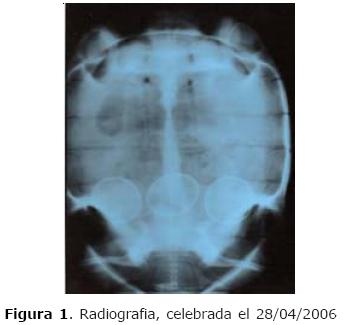

Al paciente se le realizó una radiografía en proyección ventro dorsal en la que se identificó la presencia de tres huevos. Por estar en el período reproductivo, si aconsejó observar el animal para que se diera la oviposición natural.

Se repitieron las radiografías y se han detectado, una vez mas, los tres huevos. Cuando se las comparó con las primeras radiografías, se concluyó que los tres huevos todavía estaban en la misma posición, aúnque en el segundo examen los huevos parecían estar más calcificados (Figuras 1 y 2).

Por lo tanto, se decidió realizar el tratamiento clínico con la aplicación de 0.03 ml de oxitocina (10 UI x ml) vía subcutánea en el miembro anterior del animal (Figura 3).